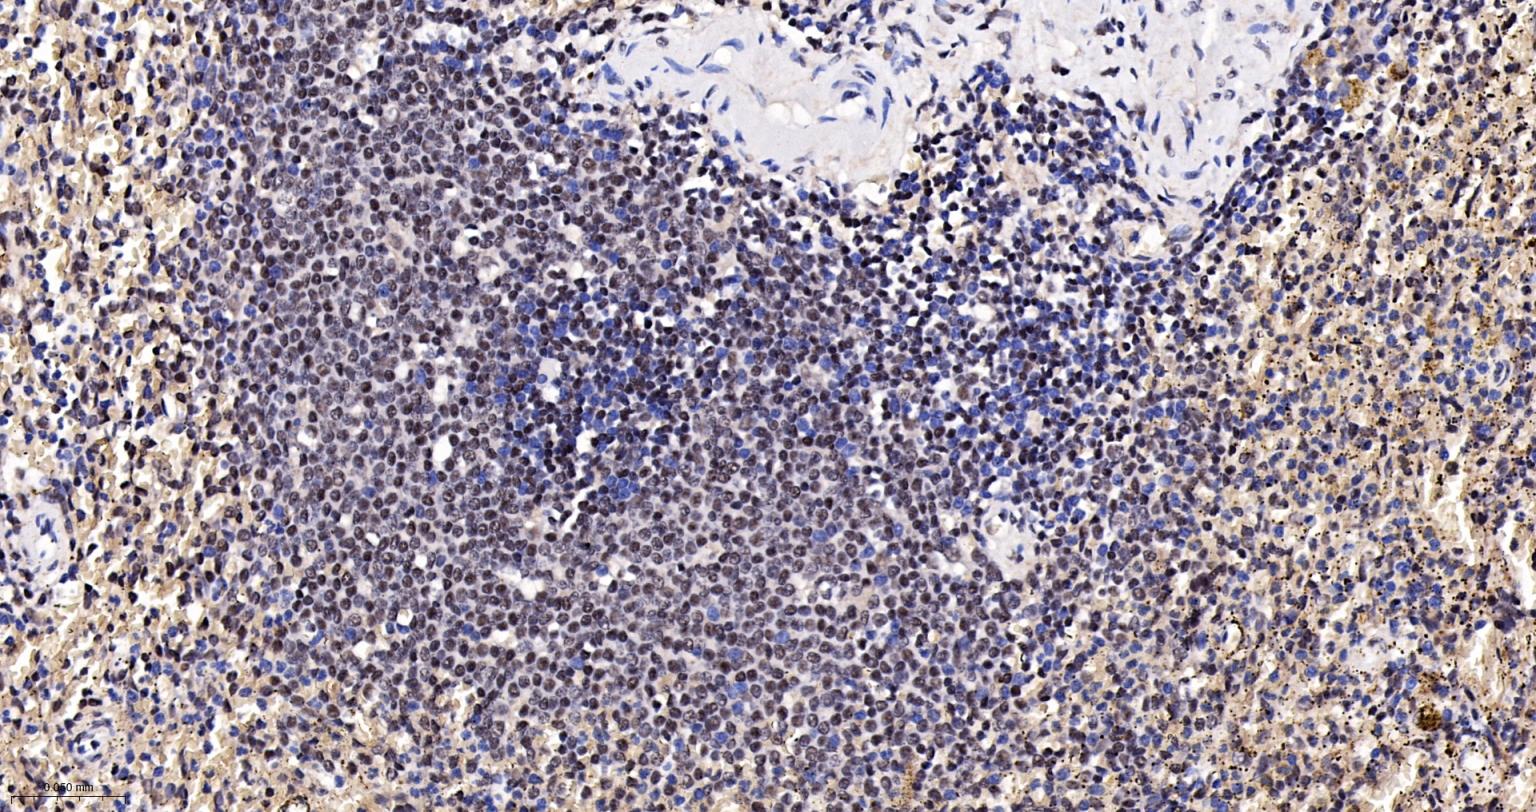

Paraformaldehyde-fixed, paraffin embedded Human Spleen; Antigen retrieval by boiling in sodium citrate buffer (pH6.0) for 15 min; The section was incubated with CTCF Monoclonal Antibody, Unconjugated (bsm-61422R) at 1:200 overnight at 4°C, followed by conjugation to the bs-0295G-HRP and DAB (C-0010) staining.